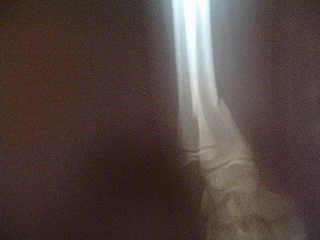

Doctor, me caí brincando en el foro

y me duele mucho la mano

( El doctor después de examinarlo le dice: )

No te preocupes, no es nada,